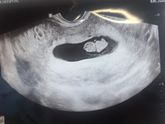

Прошла первый скрининг! Для меня это событие больше чем день рождение наверное)))

Были беременности...., но первый скрининг был по настоящему первым!☝?

А тут такая красота ? Прям шею видно ? ЧСС 160 уд/мин.

Первая встреча ? размер с кунжутную семечку ❤️ пусть тебе будет тепло, спокойно и уютно в домике ещё 8 месяцев, а потом мы встретимся ?